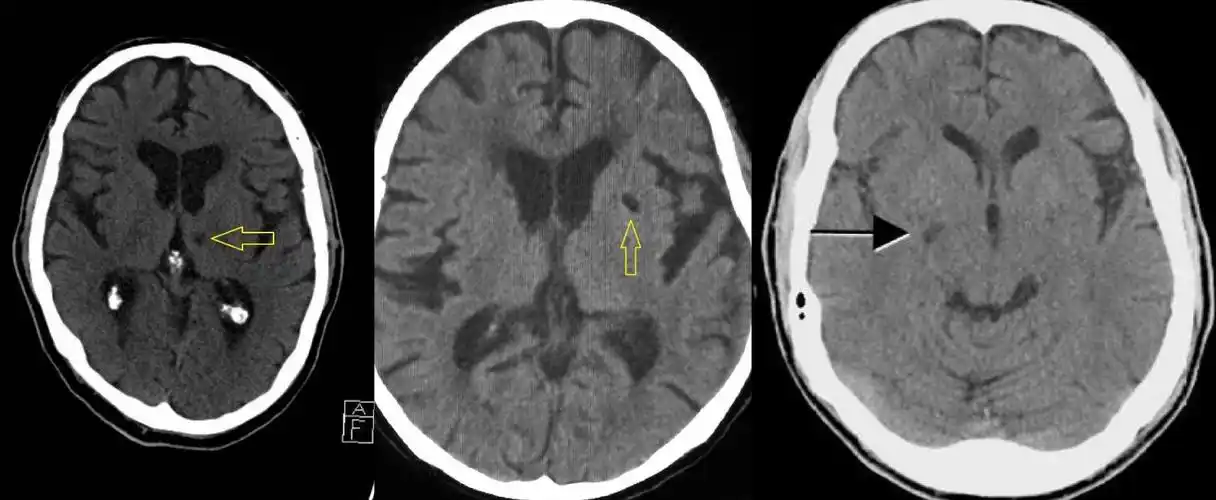

术前头颅ct可见右侧大脑中动脉血栓 aspects评分 10分

67超急性期大面积脑梗死ct平扫表现

5大ct征象诊断脑梗死

汇总超早期脑梗死ct征象